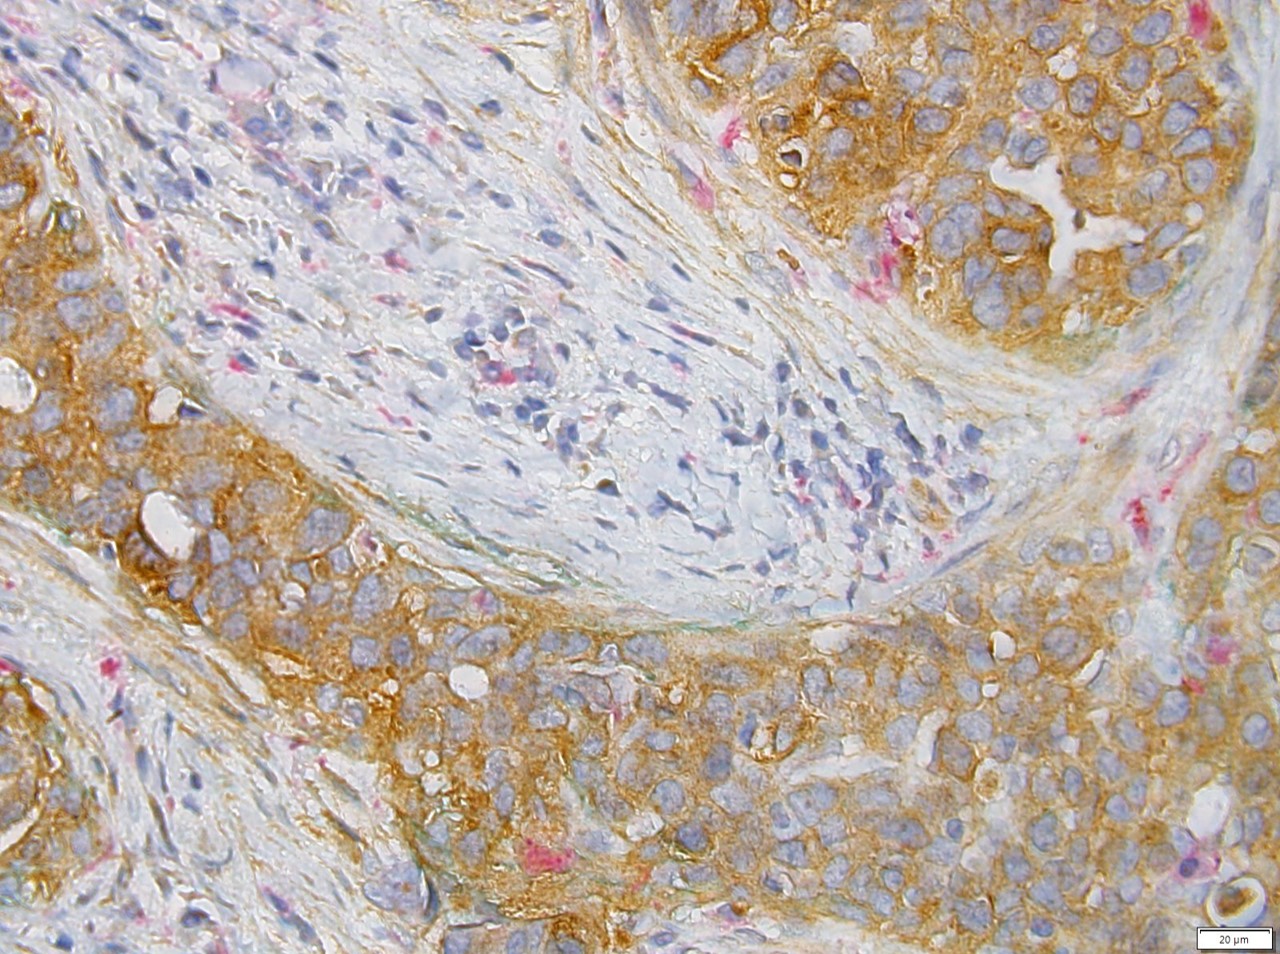

Representative image showing a DCIS tumor from a human patient expressing SEMA7A (brown) and being infiltrated by macrophages (CD68+, pink) where there is no myoepithelium (podoplanin+, green) around the tumor, suggesting areas of potential DCIS cell invasion.